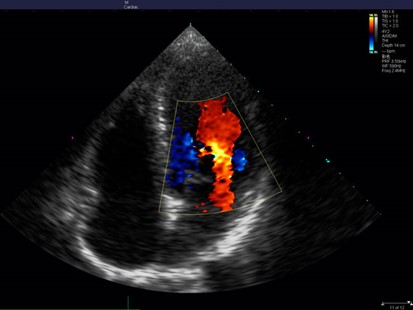

Entendiendo el Doppler